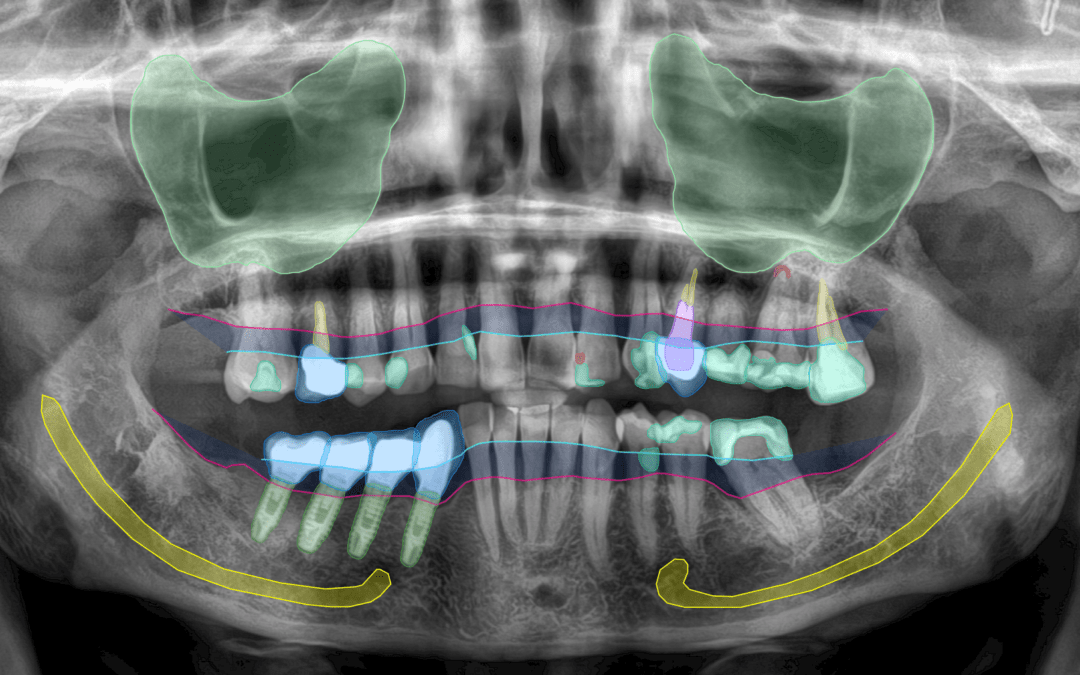

La inteligencia artificial aplicada a la odontología consiste en el uso de programas capaces de analizar imágenes y pruebas clínicas de forma muy detallada. Estos sistemas trabajan con información procedente de:

* Radiografías digitales

* Escáneres intraorales

* TAC dental en 3D

* Fotografías clínicas

* Registros de mordida y función masticatoria

Gracias a este análisis, es posible visualizar con mayor claridad dientes, hueso, encías, raíces y otras estructuras importantes que no siempre son fáciles de valorar a simple vista.

Uno de los grandes beneficios de la planificación digital es que permite obtener una visión muy completa de la salud bucodental desde el primer momento.

El análisis de las pruebas diagnósticas puede ayudar a detectar:

- Pérdida de hueso alrededor de los dientes o implantes

- Caries en fases iniciales

- Infecciones en la raíz del diente

- Problemas en la articulación de la mandíbula

- Dientes incluidos o mal posicionados

Durante este proceso se analizan aspectos como la cantidad y calidad del hueso, la posición ideal de los dientes o implantes y la relación entre encías, sonrisa y función masticatoria.